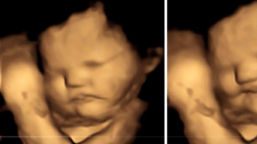

子宮嬰兒有沒有生命?3D超聲波圖片揭開秘密